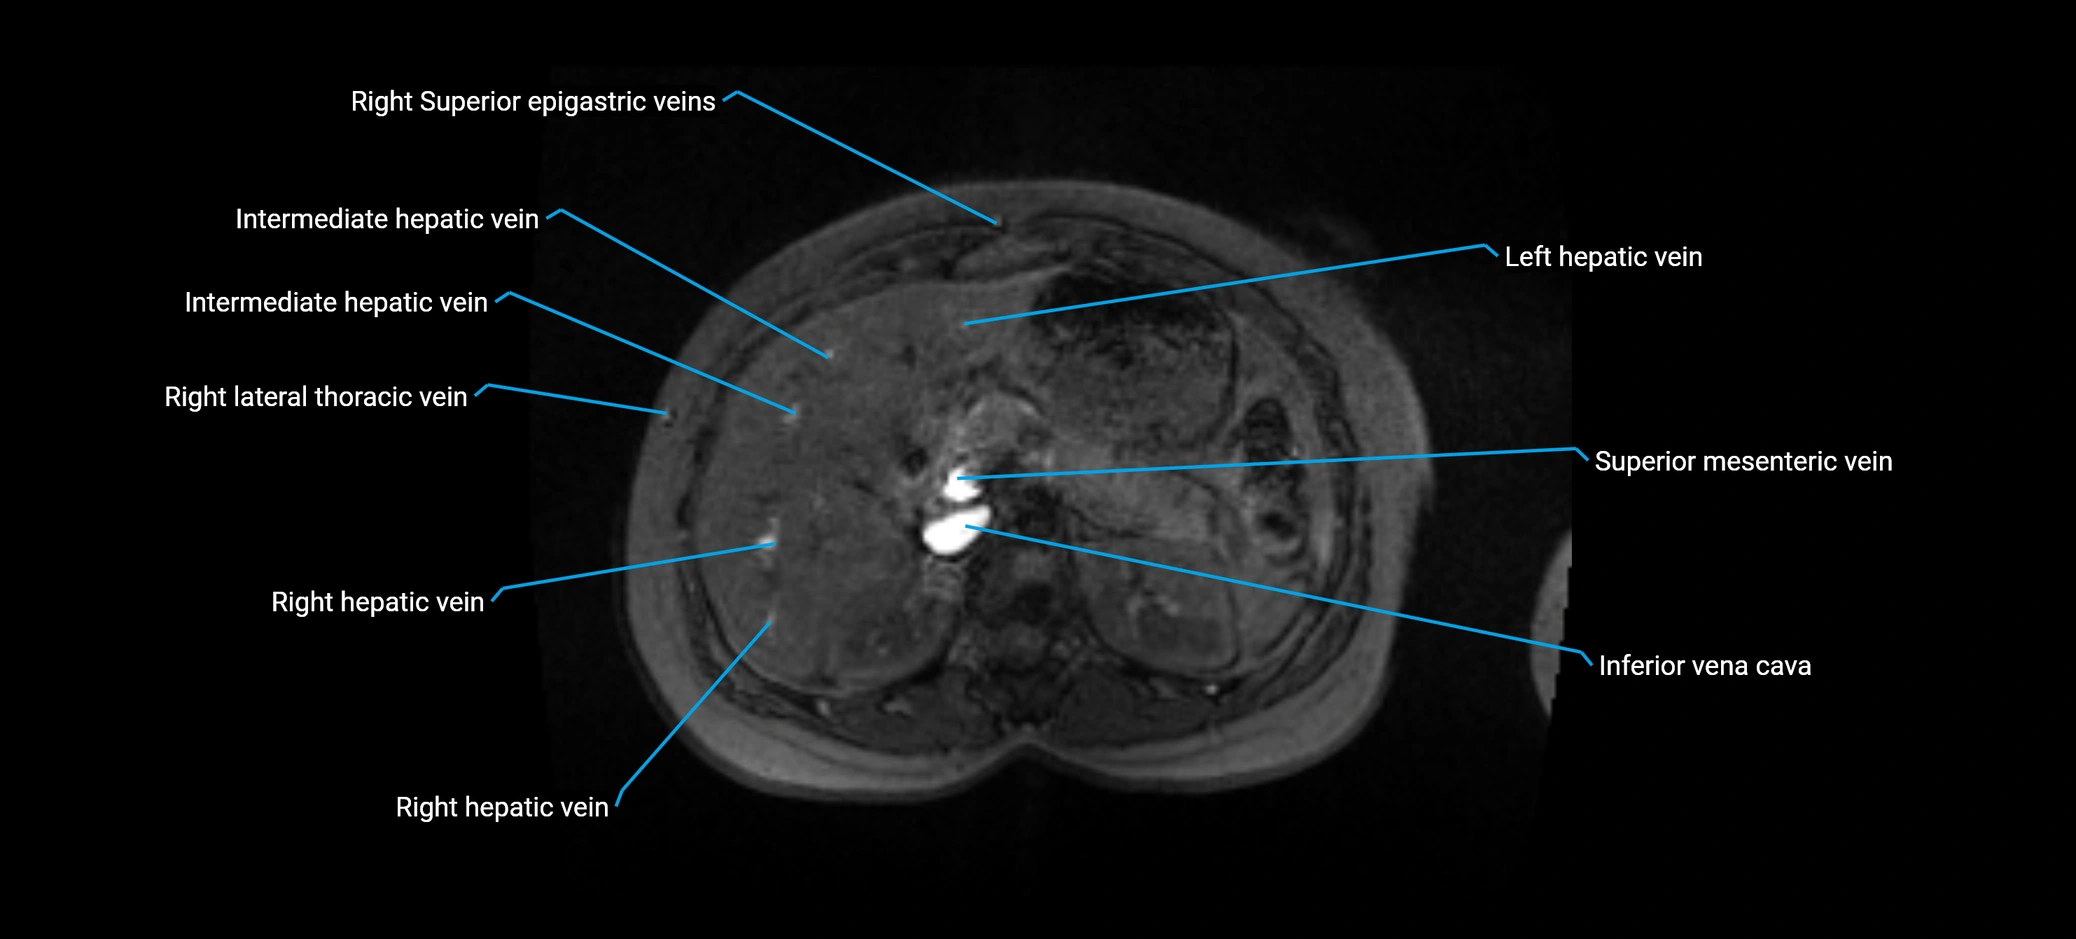

MRI image

image